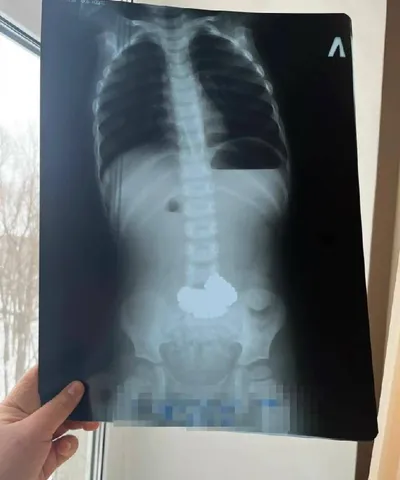

Трёхлетний житель Башкирии проглотил 206 магнитных шариков Врачи на месте не рискнули проводить сложное вмешательство и запросили помощь у коллег из Уфы. Пациента срочно эвакуировали бортом санавиаци

16 мар. 2026 г.

105.0k 643 44